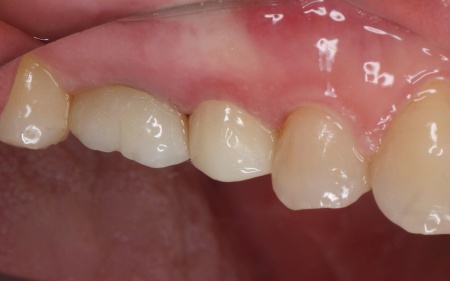

1:細菌感染した神経を取り除いてから薬を詰める「根管治療」 2:歯を長く使えるように土台をたてる「支台築造」 3:被せ物による「補綴修復」 以上のメリットとデメリットを丁寧にお伝えし、治療に同意いただきました。 まず、割れている部分をしっかりと確認し、必要な部分を除去してから根管治療を行います。 最後に、完成した被せ物を装着し、噛み合わせや見た目に問題がないことを確認して、治療を終了しています。 なお、患者様の下の歯の治療についてはこちら:https://dr-kaiya.com/blog/20260312-2/ |

治療後